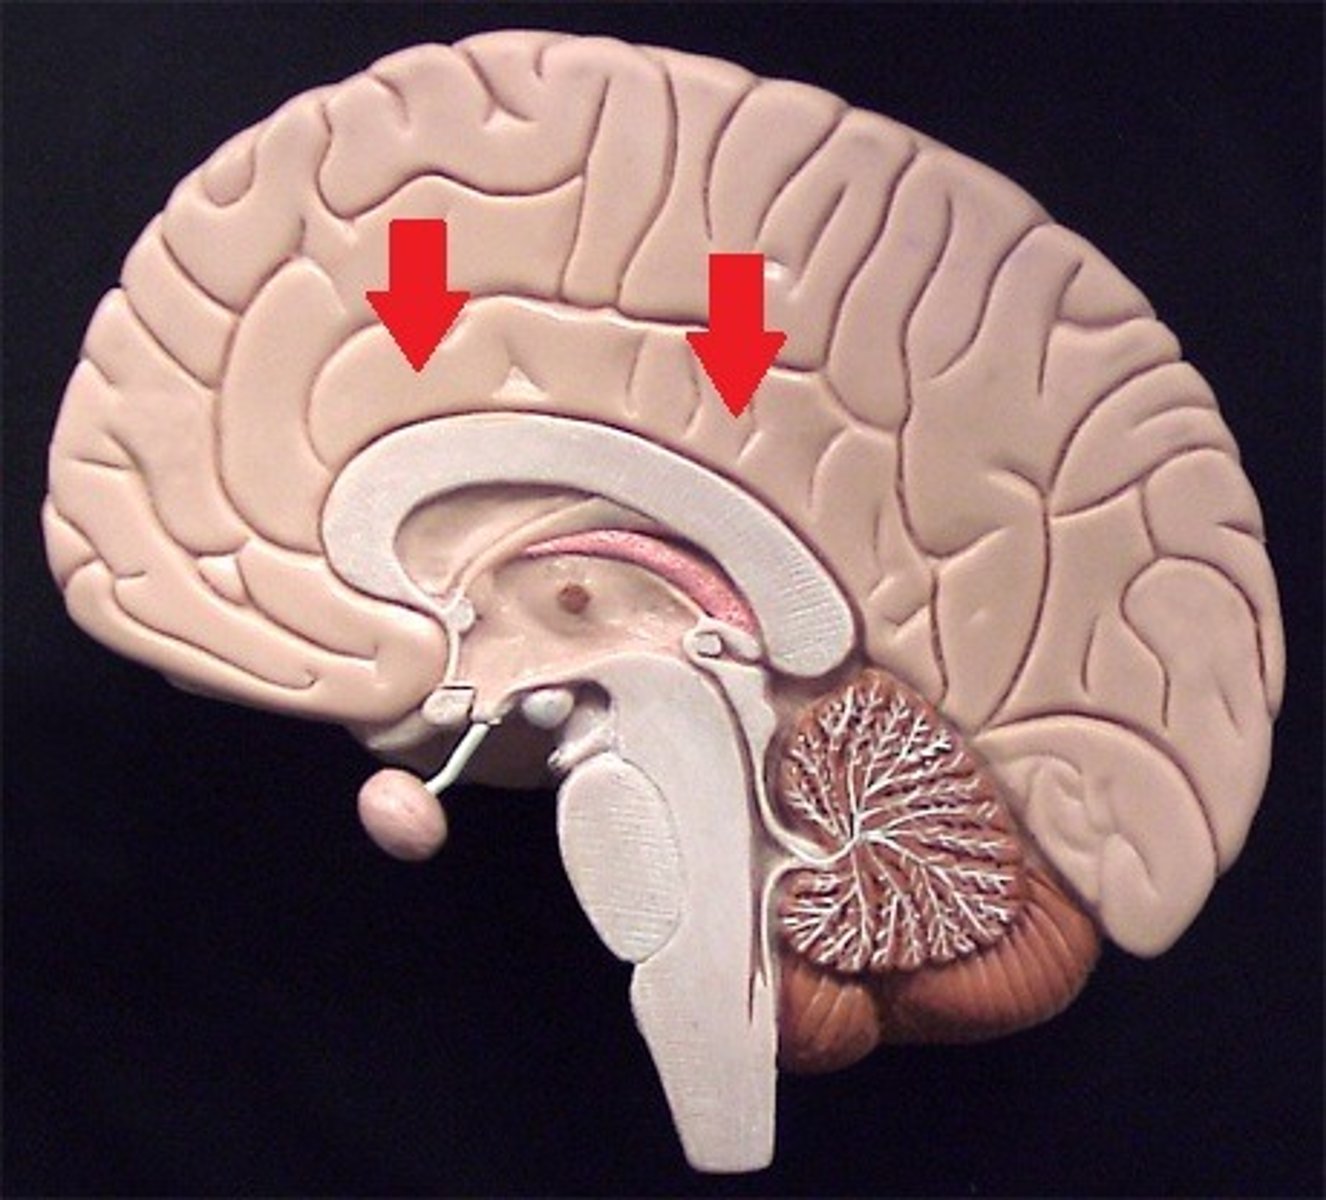

corpus callosum

A thick band of axons that connects the two cerebral hemispheres and acts as a communication link between them.